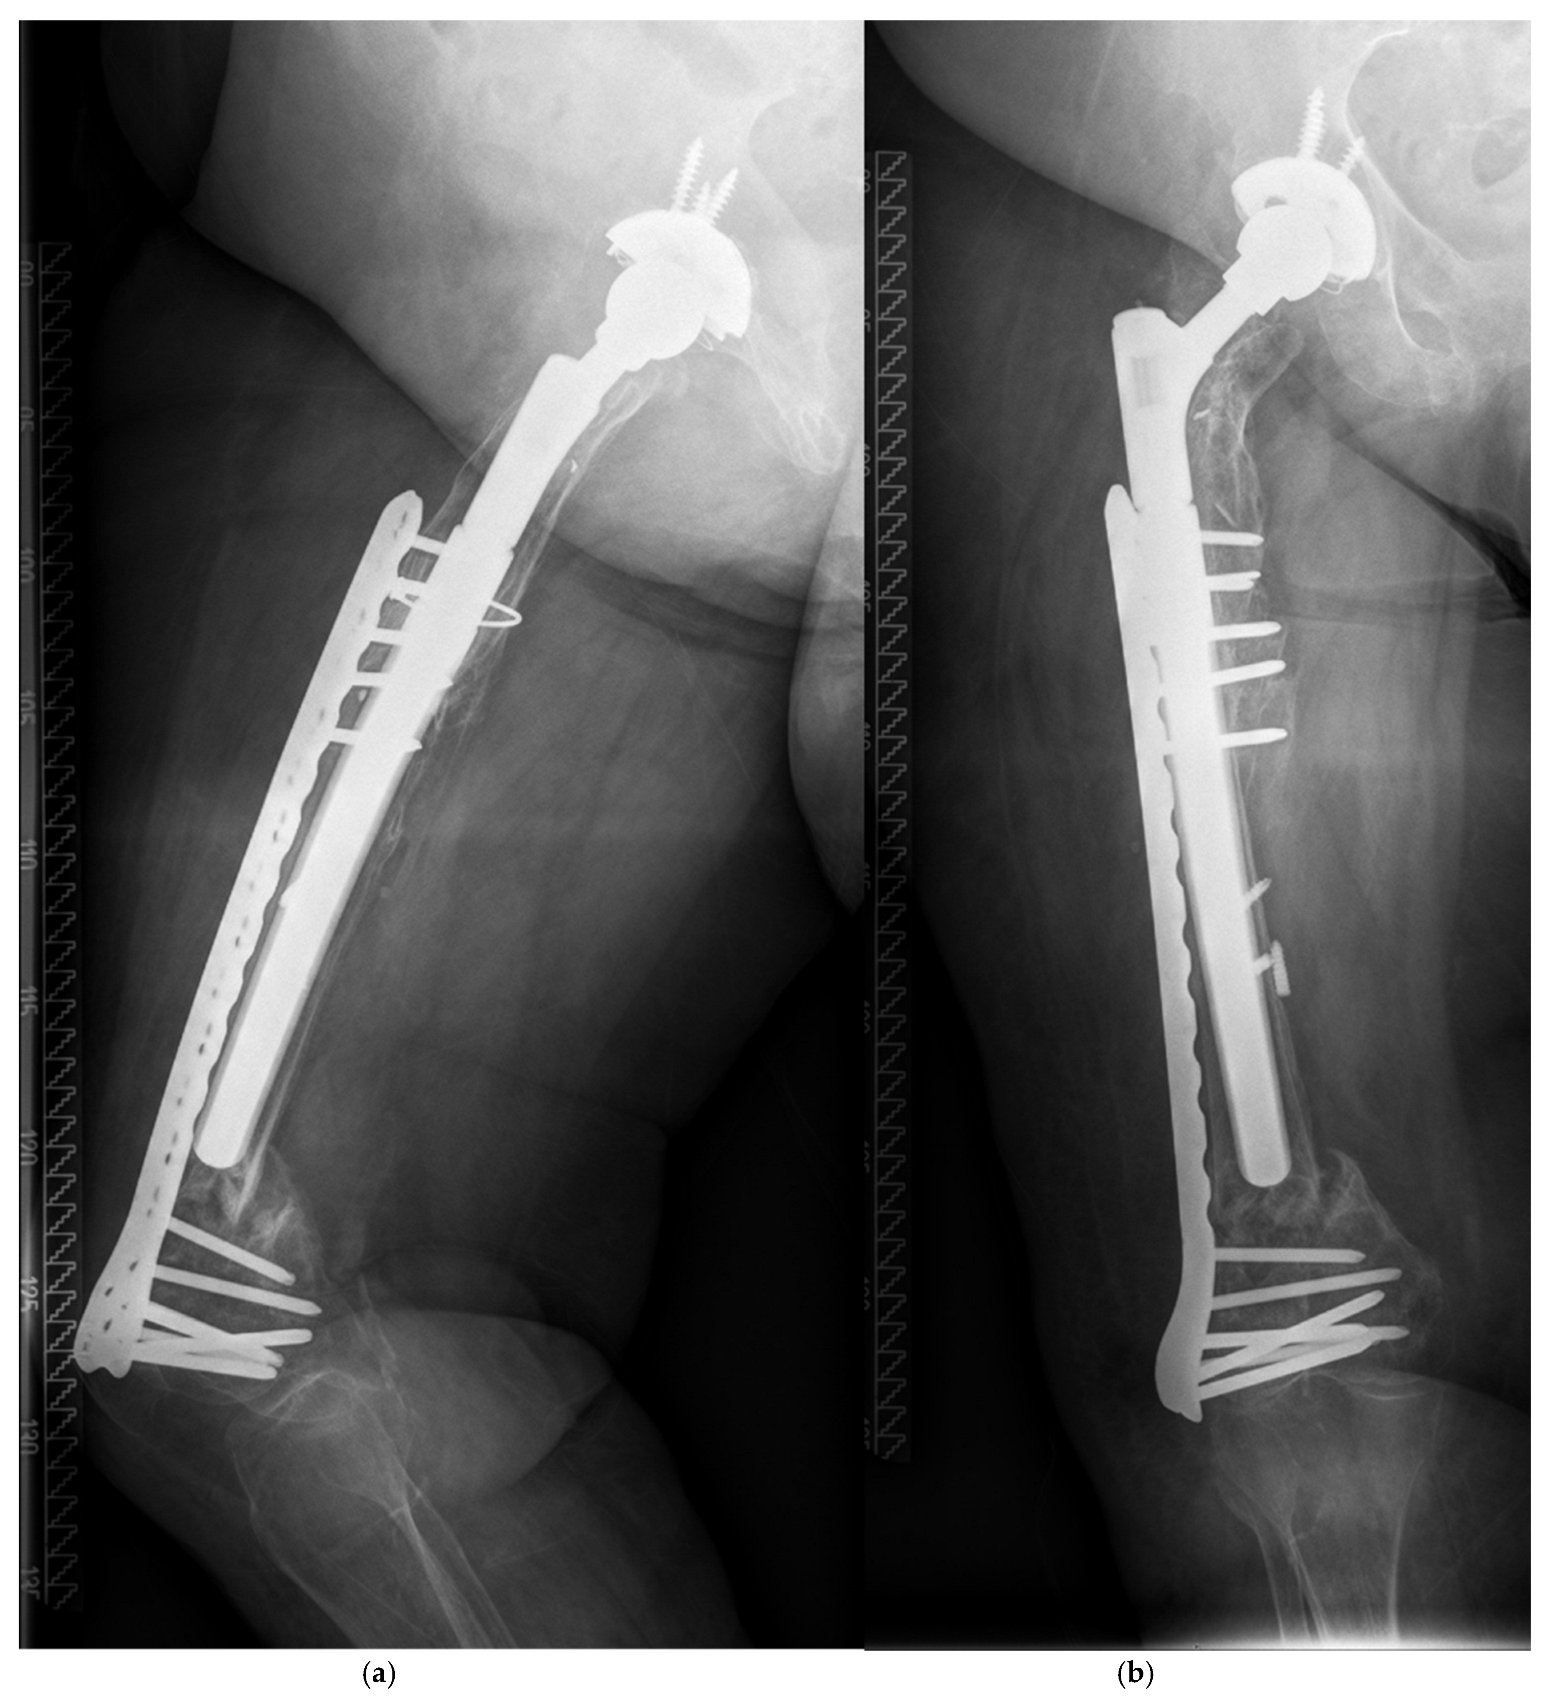

| 77, f. | TSR | 4 | TG | 20.8 | y | 4.2 | C | O (ORIF by Plate) | 290/14 |

| 68, f. | AL | 2B | TG | 22.5 | n | 0.8 | C | O (ORIF by Plate, Liss ©) | 250/18 |

| 73 +, f. | AL | 3B | TG | 34.4 | n | 8.6 | C | O (MIS by Plate, VA ©) | 290/21 |

| 75, f. | AL | 2B | TG | 25.9 | n | 9.8 | C | O (ORIF by Plate, VA ©) | 250/19 |

| 76, f. | AL | 2A | TG | 31.8 | n | 0.1 | B1 | O (ORIF by Plate, Liss ©) | 240/22 |